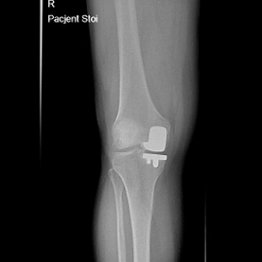

Endoproteza stawu kolanowego

Endoprotezoplastyka stawu kolanowego to skuteczna metoda leczenia zaawansowanej choroby zwyrodnieniowej kolana. Zabieg polega na chirurgicznym usunięciu uszkodzonych powierzchni stawowych i ich zastąpieniu nowoczesnym implantem – całkowitym lub częściowym – który przywraca funkcję stawu, poprawia jego stabilność i eliminuje ból. Leczenie to jest przeznaczone dla pacjentów z silnymi dolegliwościami bólowymi, ograniczeniem ruchomości, sztywnością kolana oraz brakiem efektów leczenia zachowawczego.

Możliwość zastosowania protezy jednoprzedziałowej przy mniej zaawansowanych zmianach